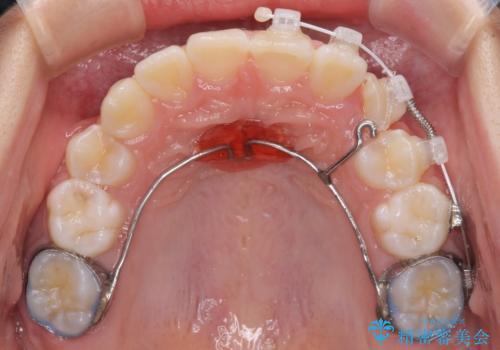

左上の犬歯が低位に埋伏しており、将来八重歯になるリスクが高いと判断されたため、補助装置とワイヤーを用いて犬歯を通常の位置まで移動させることとしました。

今後残っている乳歯が抜け、永久歯が萌出してくるため、調整可能なリンガルアーチを用いて保定を行っています。